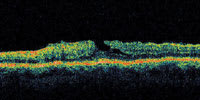

Figure 1. OCT showing early macular hole formation. The lateral separation is less than 50 μm. |

A central clinical challenge has been accurately diagnosing early macular holes which may be mimicked by many other conditions.34,35 No imaging modality has enhanced our diagnostic capability more than the OCT; superior imaging capabilities have improved diagnostic accuracy, clinical monitoring, and postoperative assessment.36-38 The OCT unequivocally demonstrates early stages of full-thickness macular holes (Figure 1), and allows distinction of pseudohole and pre-macular hole conditions in almost all instances. Fluid accumulation in early, presumed pre-macular hole stages have been corroborated by OCT observations (Figure 2). Serial images have been reported showing the progression from apparent impending macular holes to full thickness macular holes.39-42 It has depicted many other configurations that might be in the spectrum of lamellar or pre-macular hole conditions (Figure 3 and 4).